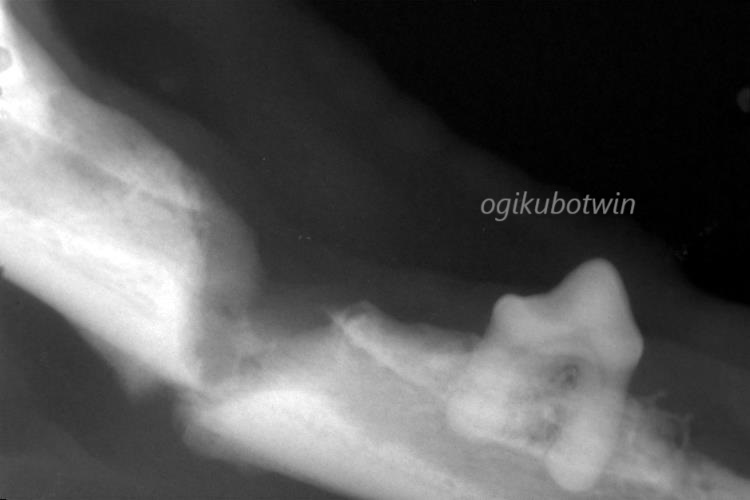

歯科レントゲンを撮影したところ右下顎第一後臼歯(奥歯)の近心根で歯周病が進行している部分の顎骨が骨折していました。

2週間後の検診では鎮静下でレントゲンを撮影したところ骨折部位の骨増生が認められ経過良好です。

鎮静下でのレントゲンでは動揺が少しある程度で経過は問題なしと思われます。